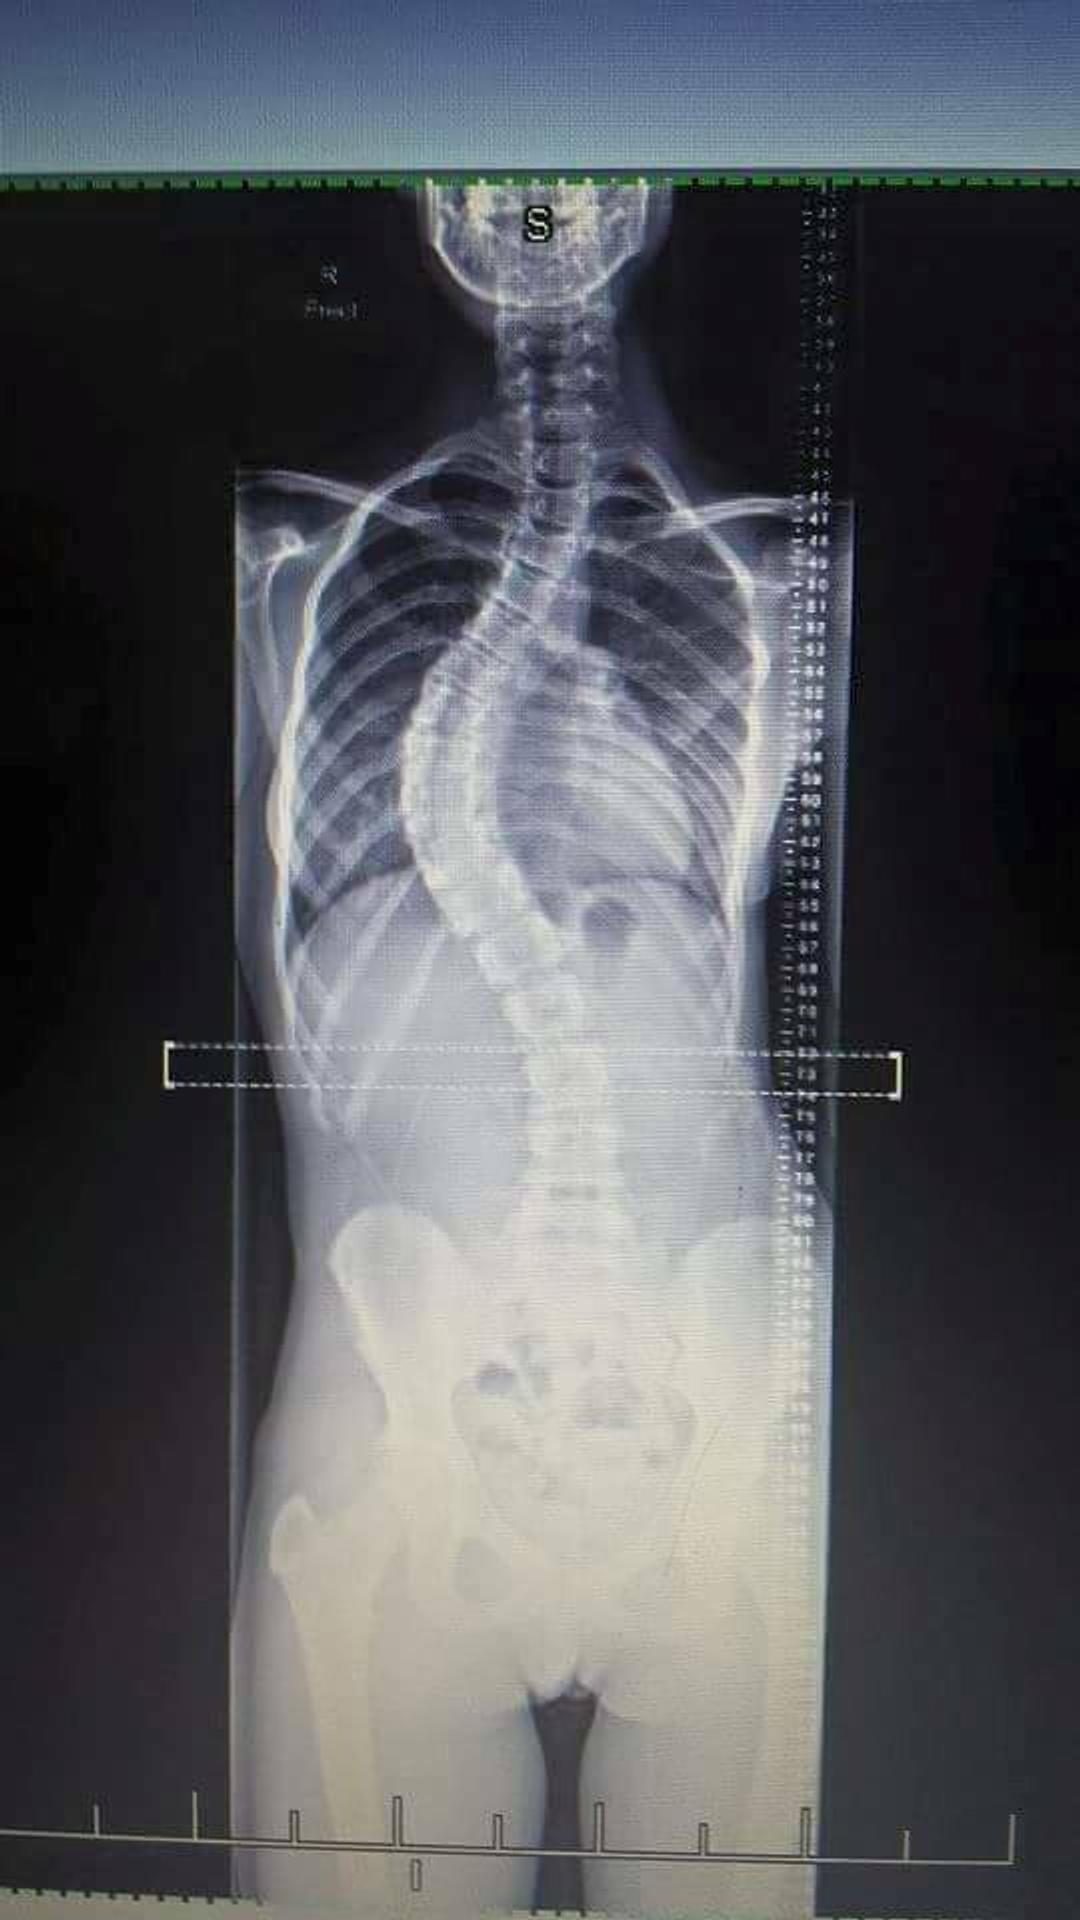

Galéria: Dievča trpí vzácnou chorobou. Chrbticu mala o 55 stupňov vykrivenú